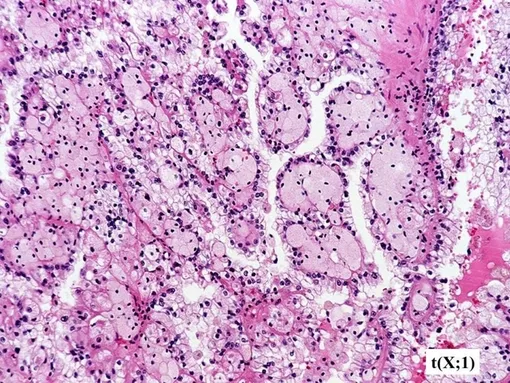

Транслокационная карцинома почки (tRCC) — редкое и агрессивное заболевание, поражающее детей и молодых взрослых. При делении клетки (митозе) хромосомы могут ошибочно обменяться своими фрагментами. В этом случае ген TFE3 может сливаться с другими генами. В результате образуются активный ген, который кодирует химерные белки-онкофузии. Эти белки постоянно активируют гены роста и провоцируют развитие опухоли. Это было известно, но ученые не понимали механизм, с помощью которого химерные белки запускают бесконтрольный рост опухоли.

Теперь ученые обнаружили, что химерные белки привлекают молекулы РНК для создания каркаса особых структур — конденсатов. Эти капли собирают важные молекулы в плотные карманы, которые становятся центрами активации генов роста опухоли. «РНК — не просто пассивный посредник, а активный участник строительства этих конденсатов», — отметил профессор Юн Хуан, старший автор работы. Ученые также выявили и другой важный белок — PSPC1, укрепляющий эти капли и усиливающий их роль в развитии опухоли. Работа опубликована в Nature Communications.